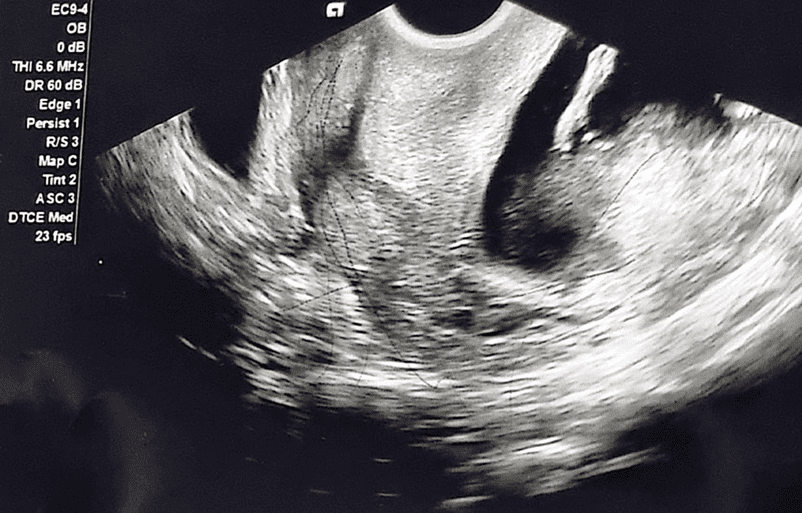

28-year-old female G7P3+0+3+3 12+4 weeks of gestation previously healthy with no known medical or surgical history presented to the outpatient department for her regular antenatal follow up. During her first visit she mentioned that she is having difficulties in passing urine. Baseline investigations including complete blood count (CBC), renal function test (RFT), urine routine and culture were done to look for urinary tract infection which was ruled out. However, the patient was given an ultrasound appointment to look for any underlying urinary tract pathology along with urology outpatient clinical referral. However, patient came after few days with worsening symptoms leading to complete urinary retention thus the patient admitted to the hospital and Foleys catheter was inserted. Our differential diagnosis was the following: Urinary tract infection, Urinary tract obstruction attributed to a urological cause i.e. nephrolithiasis or attributed to a gynecological cause i.e. large uterine fibroid. During hospital stay urine culture was repeated which came back with no growth. An Ultrasound was done by an obstetrician which revealed an acutely retroverted uterus with a fetus matching gestational age calculated from the first day of her last menstrual period (LMP) as shown in Figure 1 and 2.

Figure 1: Transvaginal ultrasound revealing an acutely retroverted uterus with a picture of uterine incarceration